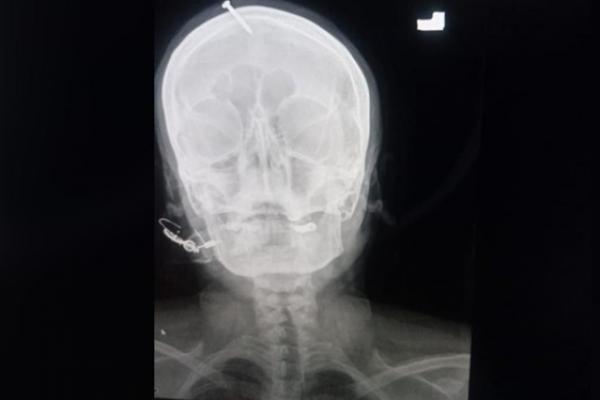

Inginkan Anak Lelaki, Tabib Pasang Paku di Kepala Wanita Pakistan Seorang tabib menancapkan paku di kepala seorang wanita hamil dengan jaminan akan mendapat anak laki-laki. Foto: twitter/ArabNews

Sinar-X menunjukkan paku lima sentimeter menembus bagian atas dahi wanita itu tetapi tidak mengenai otaknya. Khan mengatakan palu atau benda berat lainnya digunakan untuk menancapkannya.